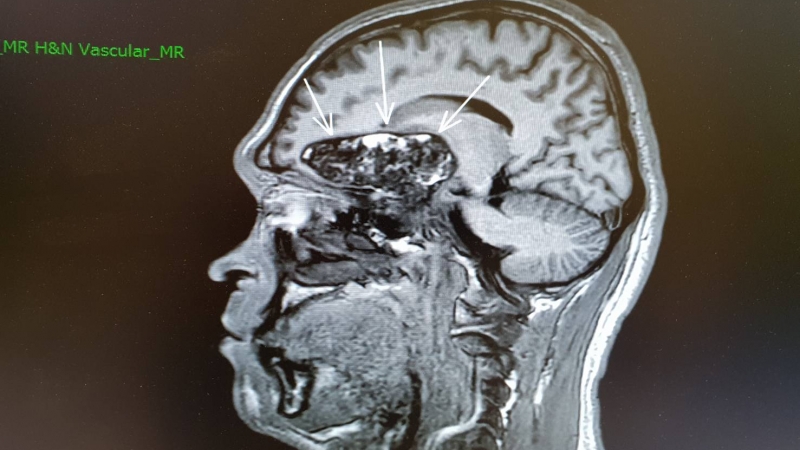

39歲的陳先生,去年下半年開始常聞到腐爛臭味,讓他吃飯總是沒胃口,但周遭親友卻都表示沒聞到,讓他開始懷疑是身體出問題;在陸續接受腸胃鏡、甚至到耳鼻喉科清洗鼻腔,狀況均未改善,直到前陣子前額頭出現劇痛,經腦部磁振造影後,發現腦中有顆近6公分的腫瘤,更因為腫瘤壓迫到大腦的嗅覺神經,讓他產生嗅幻覺,才會聞到旁人聞不到的臭味。